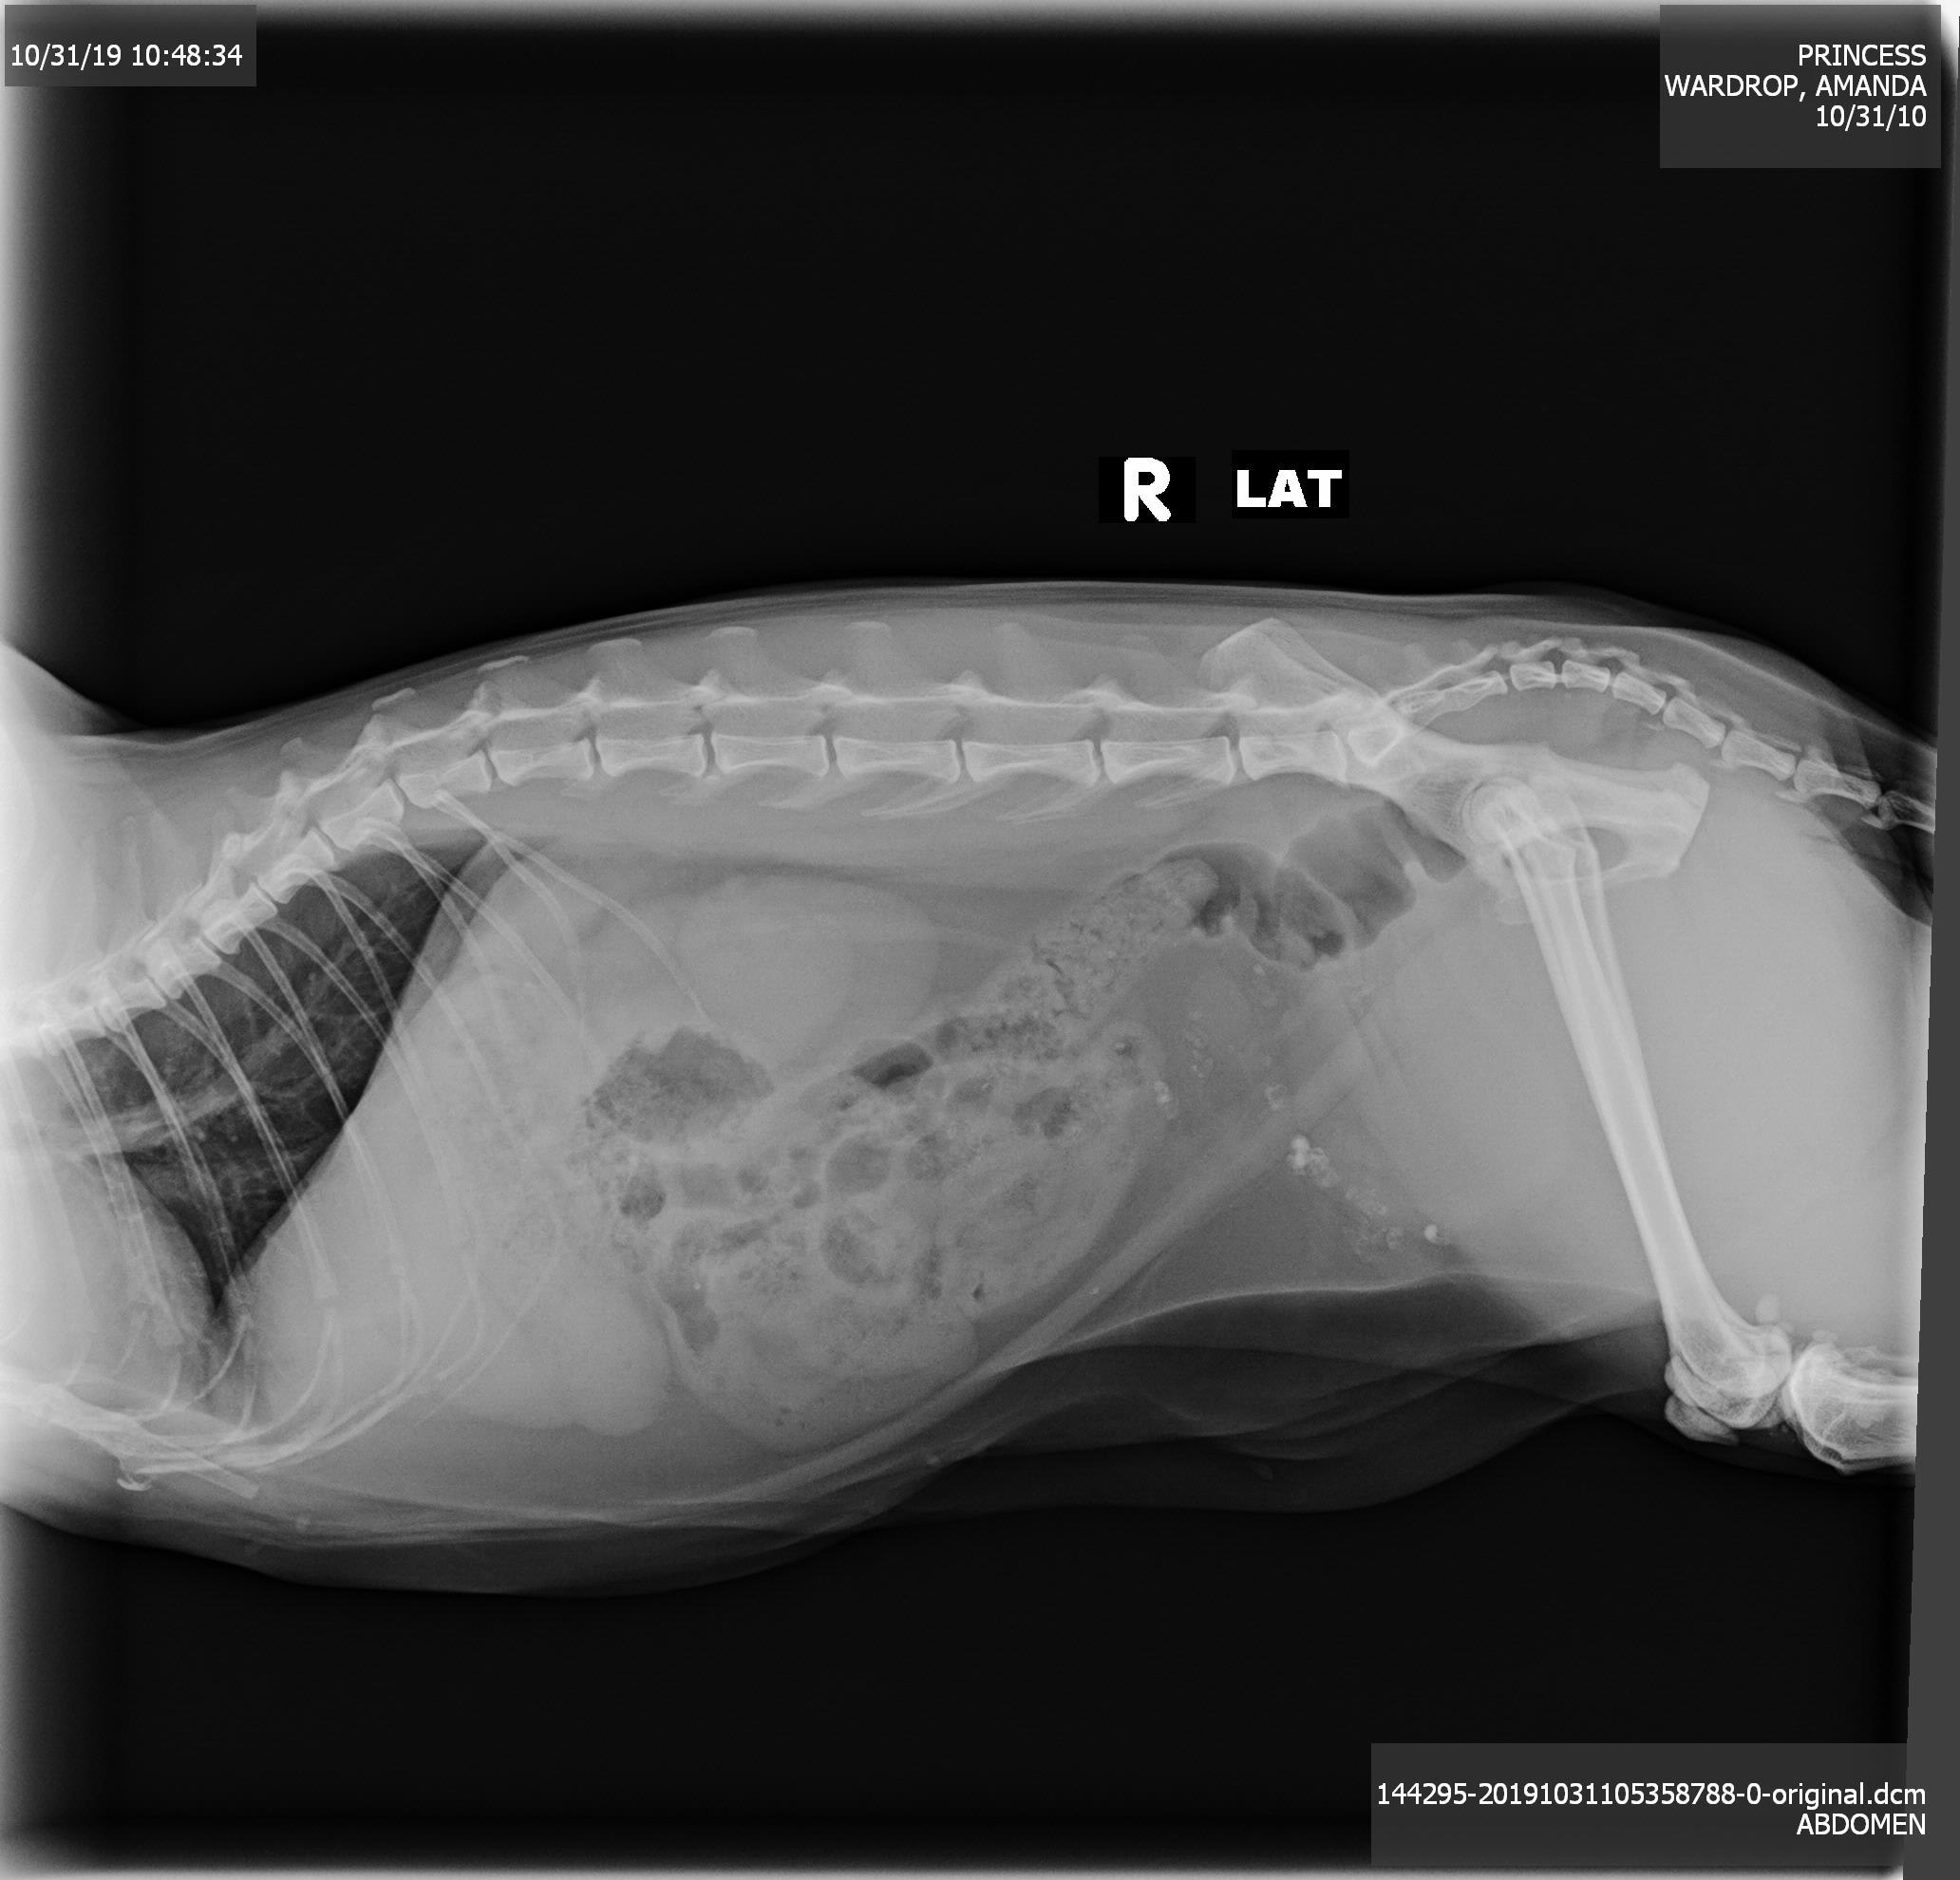

Hi, can someone please give me their opinion of this? My cat is having issues using the bathroom. I got this X-ray done and she was put on medicine (orbax) and something else. She seems to still have issues but I believe she may have stones? Do you see anything? I recently had her started on hills c/d prescription food.

Hi there and thank you for using Petco Pet Education Center, formerly Petcoach to address your concern. There are definitely radiopaque dense gravel-like objects near the bladder and cranial to it as well. It would help to provide the x-ray where she is laying on her back as well. Multiple views on x-rays help pinpoint locations of objects if there is doubt as to where they are located. I would say that this looks to be near the bladder but not within the actual bladder itself because the same dense material can be found forward to the bladder on this x-ray, so it is likely GI tract. If you can provide a second view that would be great. It also appears that she has quite a bit of fecal material in her intestines. Is she constipated right now? If so, she may need an enema and stool softener. Please let me know if you have any other questions or concerns and I would be more than happy to help you further.